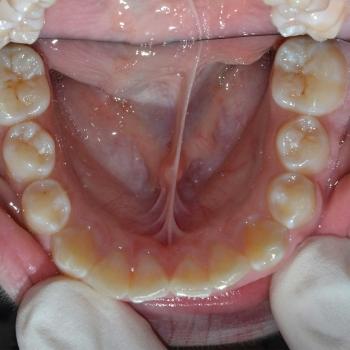

Gergő és édesanyja fogorvosi javaslatra keresett fel, a bal felső 2. kisőrlő hibás pozíciója miatt. A konzultáció során egyértelművé vált, hogy az előbb említett fog helyét teljes mértékben elfoglalták az előtte, illetve mögötte elhelyezkedő fogak, gyakorlatilag 0mm helyet hagyva a probléma megoldására. Ilyen esetekben felmerül a szájpadi irányba kiszorult fog eltávolítása, de a felső fogívben tapasztalható résesség a helyteremtés mellett szólt.

A kezelés első lépéseként Frog készülékkel hátrafelé mozdítottuk a bal felső első nagyőrlőt, ezzel elrendezve a nagyőrlők érintkezését, másfelől 4mm helyet teremtve a második kisőrlő számára. Ez a hely még nem volt elegendő, így rögzített fogszabályozóval zártuk a nagymetszők közötti, illetve az első kisőrlő előtti rést, mellyel további 2.5mm helyet nyertünk. Az így már 6.5mm-es rés elegendő volt ahhoz, hogy a kiszorult kisőrlőt bemozdítsuk a kívánt pozícióba, ezzel kialakítva egy funkcionálisan megfelelő és esztétikus felső fogívet. Mivel a harapás korrekciója, azaz a funkció helyreállítása kizárólag a felső fogív kezelésével is kivitelezhető volt, így a szülők nem kérték az alsó fogív torlódásának a megoldását.